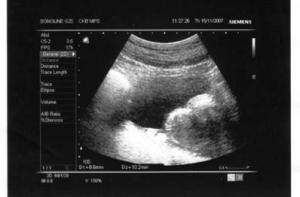

Согласно предложенным поправкам, женщина также должна пройти ультрасонографическое обследование или услышать сердцебиение ребенка при помощи доплерографа. По мнению депутатов, врач должен рассказать женщине не только о последствиях аборта, но и о развитии ребенка в утробе матери.